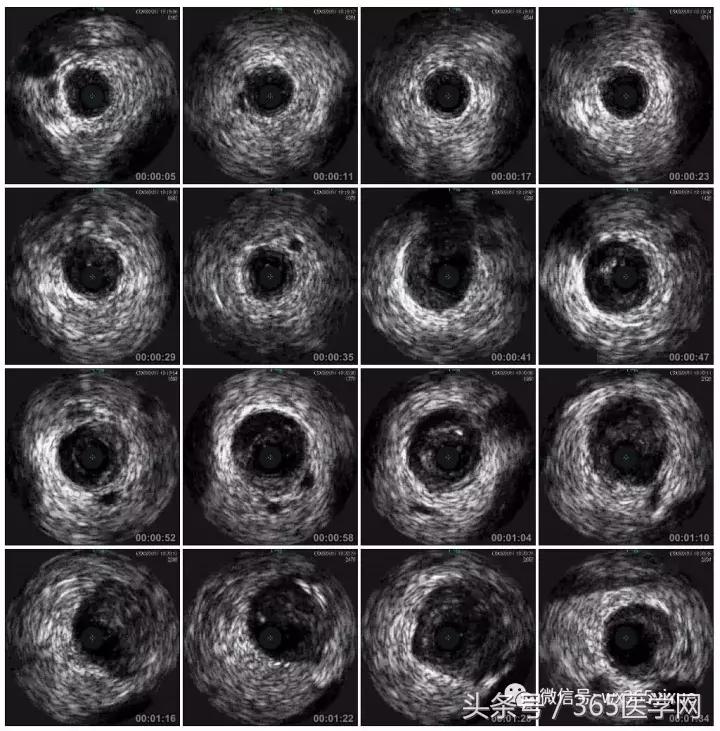

RCA闭塞段球囊扩张后IVUS

支架术后IVUS